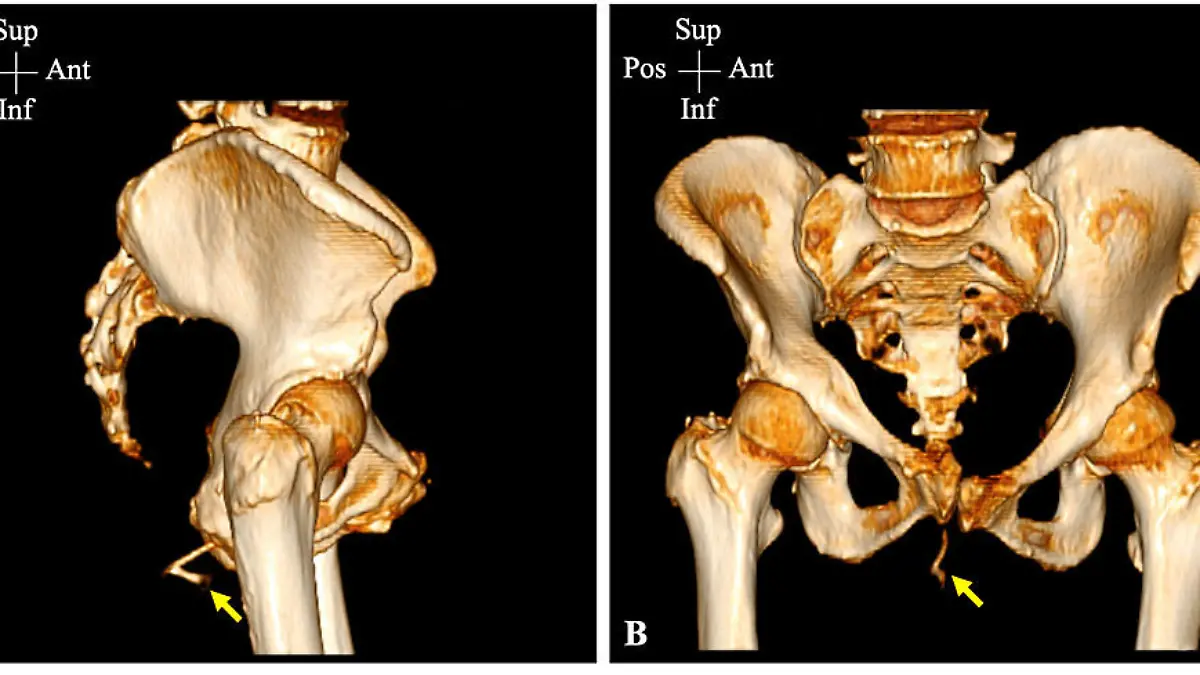

Zwar hatte es der knochige Übertäter fast geschafft, den Körper der Frau ohne Schaden zu durchqueren, am Ende verkeilte er sich aber so, dass er aus ihrem Po herausragte. Die Frau wurde kurzerhand ins Krankenhaus eingeliefert, wo eine Computertomographie (CT) schließlich die vollen Ausmaße ans Licht brachte: 5 x 2,5 x 3 cm groß war der Hühnerknochen, wie die medizinische Fachzeitschrift „Cureus“ berichtete.